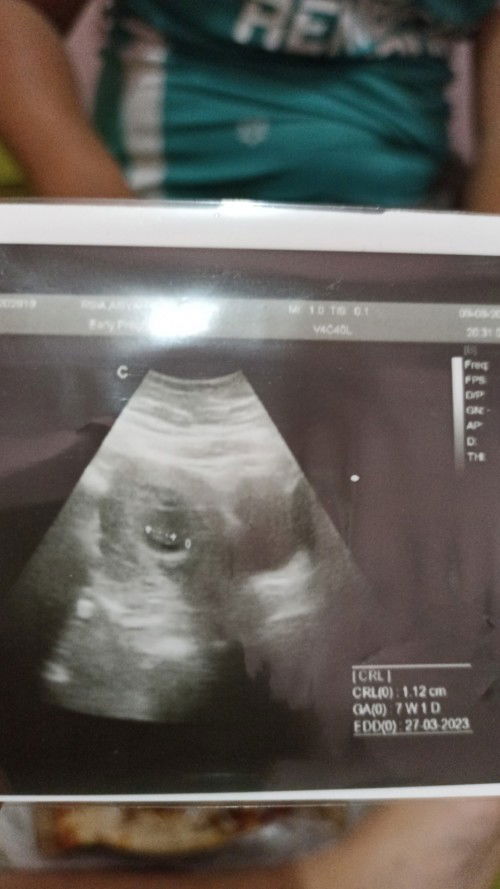

Janinku tdk berkembang stuck di 7 week

Kehamilan ke 2 aku, dan lagi lagi hrus nelan pil pahit dokter saranin aku buat kiret lagi krn dri HPHT yang seharusnya 12 week tp di usg msh termonitor 7 week. Tp aku merasa janin ku masih ada dia msh hidup aku ngga ngerasain sakit dan pendarahan hebat sewaktu kehamilan pertama.. kalau aku nolak kiret apakah dia akan hidup??#bantusharing #ingintahu #firstmom #pleasehelp